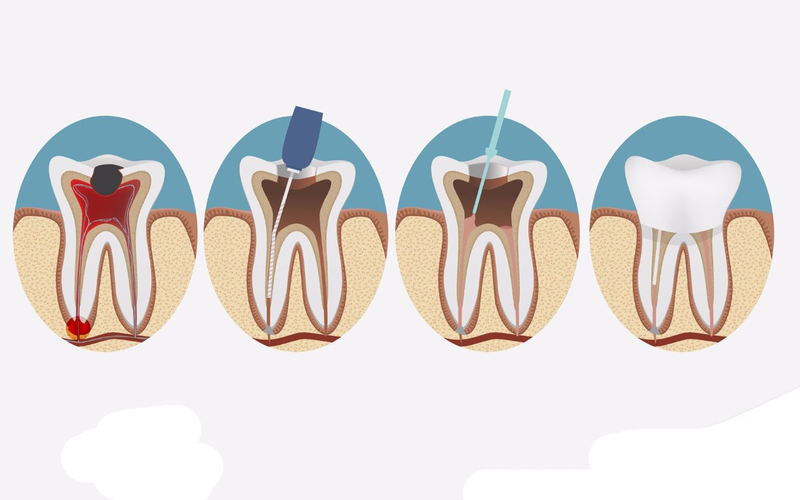

3. ĐIỀU TRỊ TỦY (NỘI NHA)

Làm sạch triệt để tủy viêm, chấm dứt cơn đau nhức dữ dội ngay lập tức. Kỹ thuật nhẹ nhàng giúp bảo tồn răng thật tối đa.